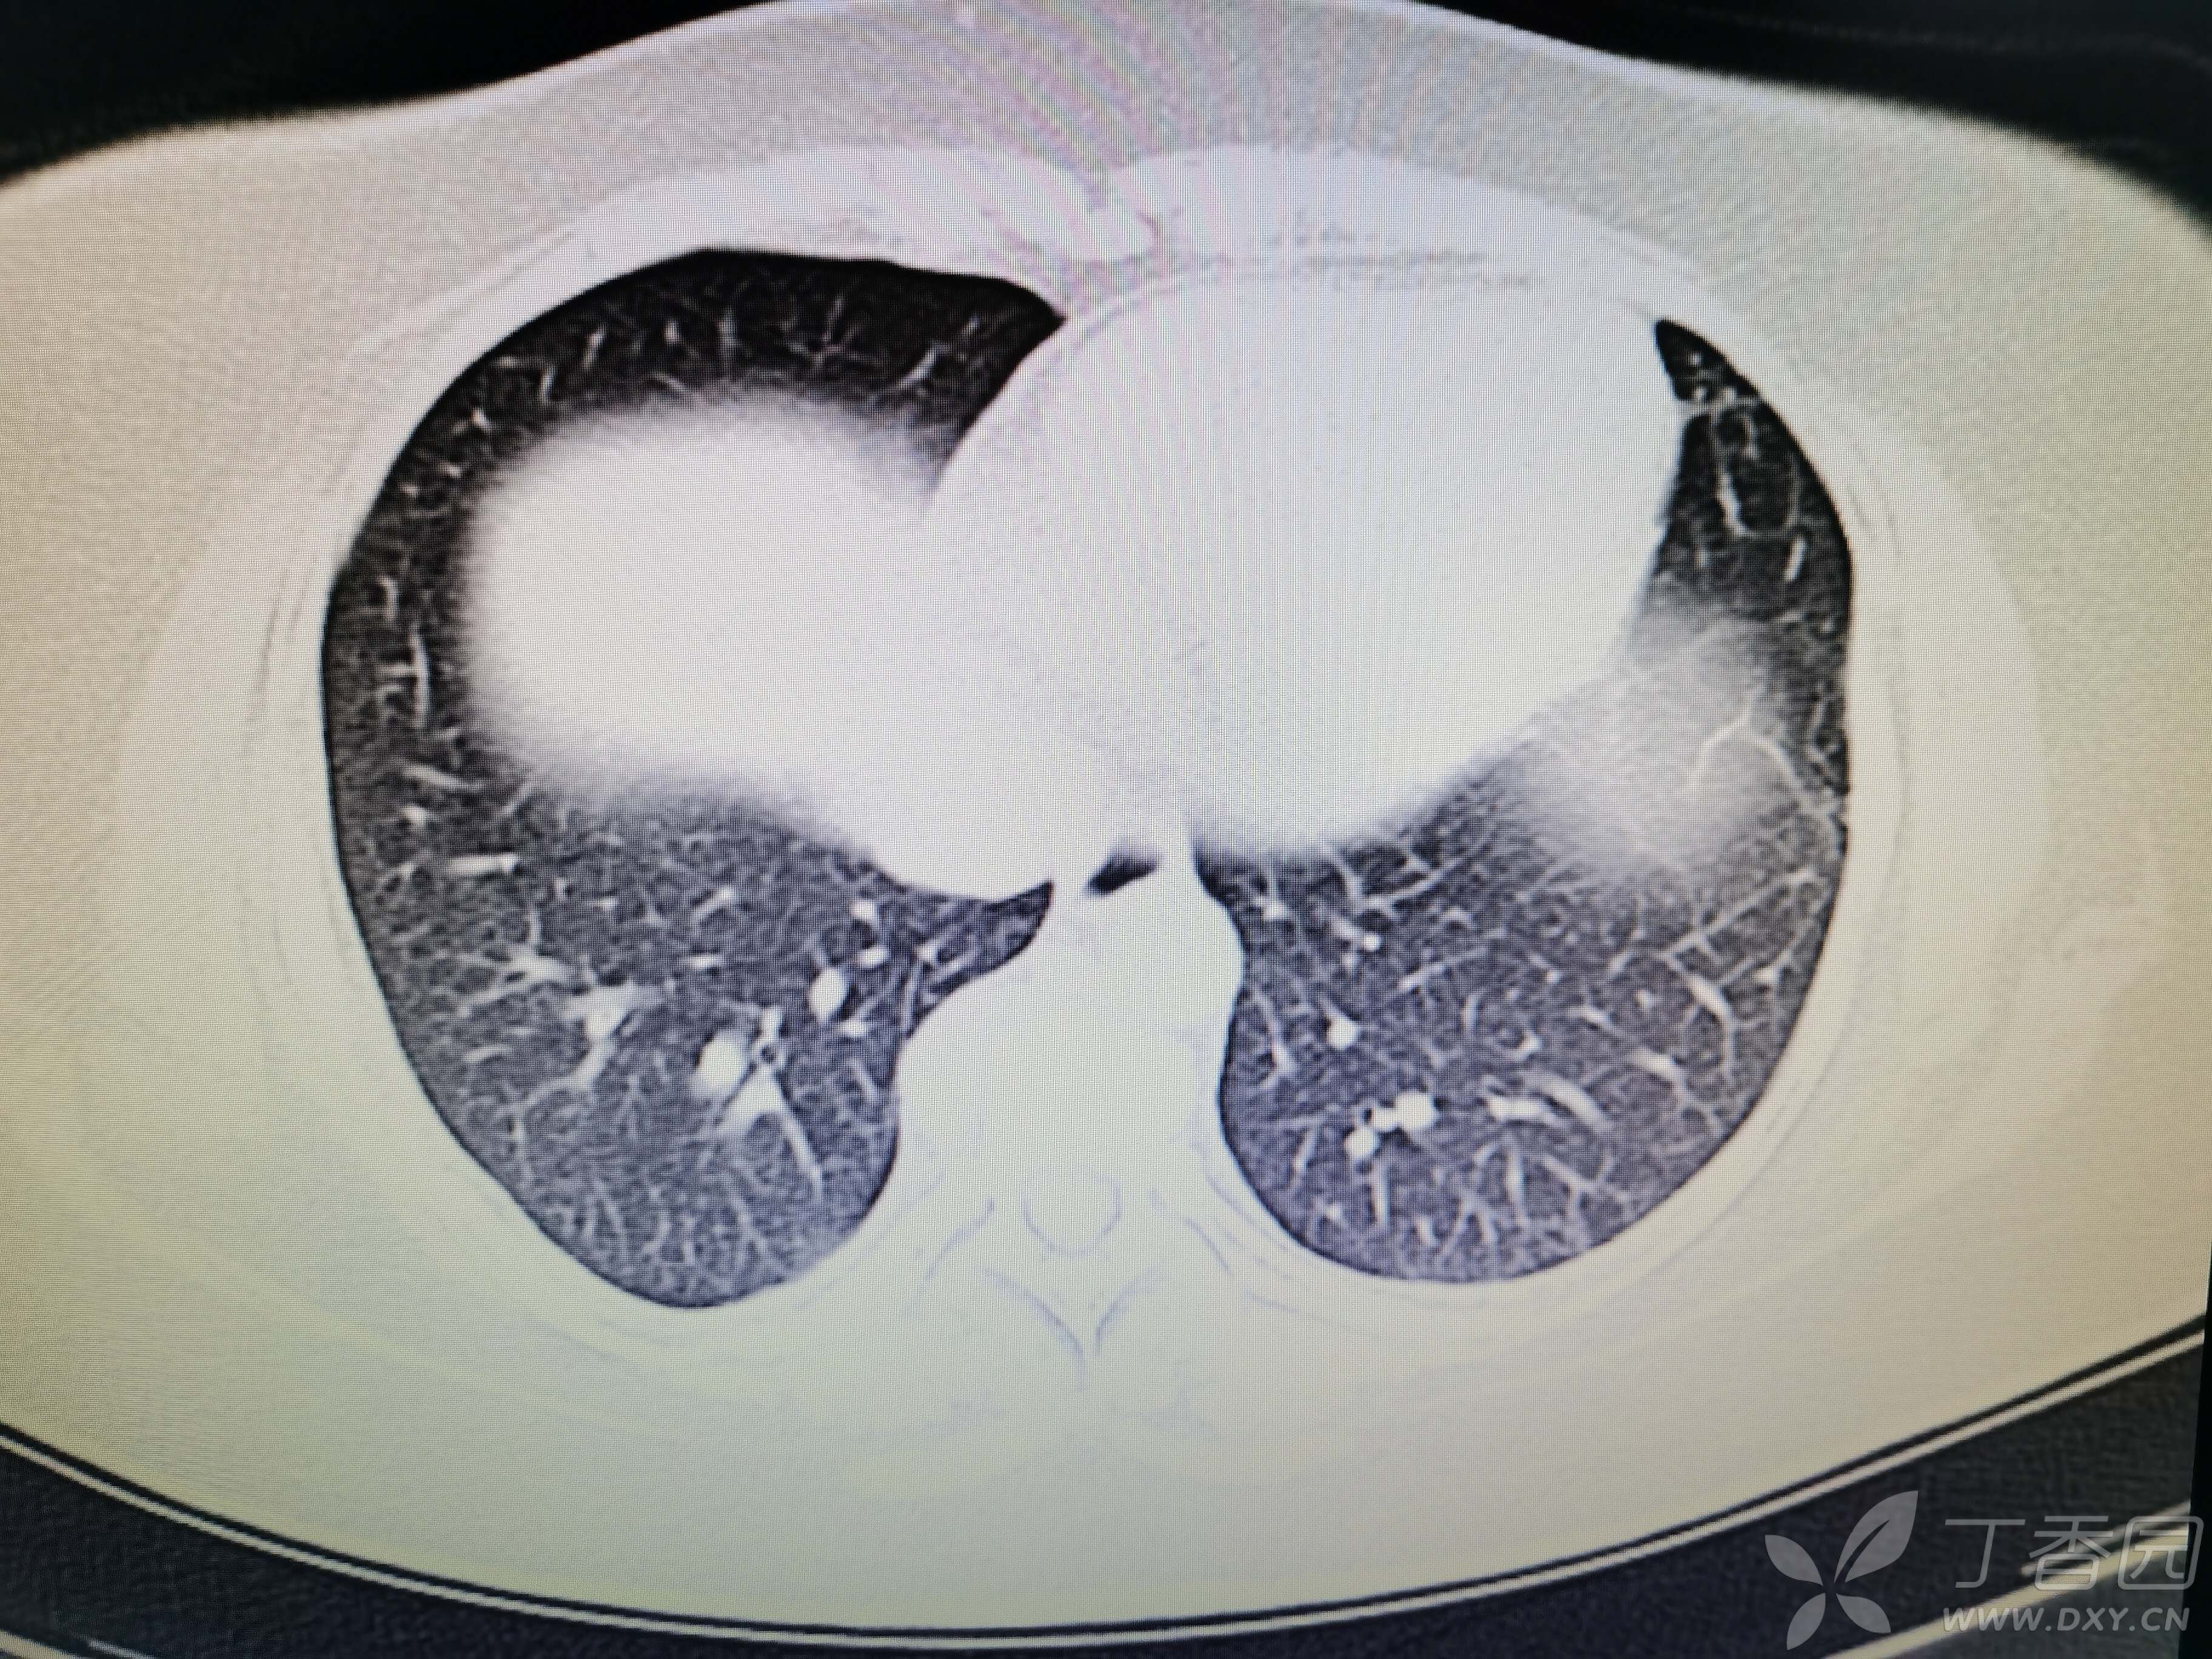

基本信息:女,三十几岁,印度人。。

胸部CT:

如题:猜肺部病灶病理。。